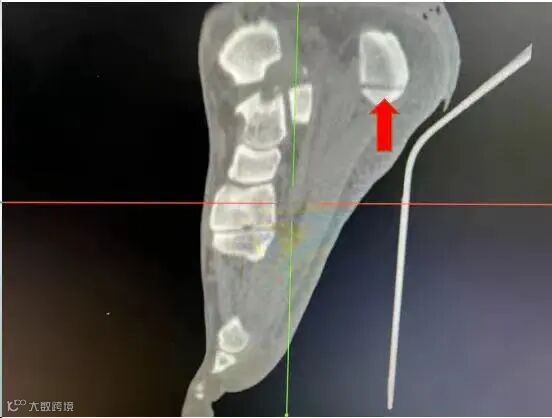

CT结果显示切割伤口深达跟骨3厘米,可能有碎骨存在。救治小组考虑到脚割伤出现大出血必须先止血,如果失血过多会影响生命,救治小组讨论决定,立即予以查找到出血动脉结扎止血清创缝合。

外科韦成业医师主刀手术,术中查找到4处直径约1毫米动脉喷血点,马上结扎止血,术中可见并处理2粒直径约1毫米碎骨,仔细检查可见被切的骨骼肌肌腱和肌腹大部分呈纵向,术中对受伤跟腱、肌腱和肌腹做修复处理,对切缘各层仔细分层对齐缝合,经过近1小时手术,终于成功结扎止血缝合切口。